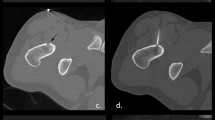

Interactive lesion localization, instrument guidance, drilling, and positioning of the laser fiber into the opened tumor were guided in near real-time imaging with a fast T1-w turbo spin echo (TSE) sequence (TE/TR 5.7/200 ms, TF 7, fa 90°, scan duration 3 s). A MRI-compatible 4-mm bone biopsy drill (Invivo, Schwerin, Germany) was used to enter the nidus with freehand technique (Fig. 3). An experienced pathologist analyzed the bone specimen. An 18-g coaxial needle (Somatex, Teltow, Germany) was introduced through the biopsy access channel with real-time MRI. The needle position was then verified with a PD-w TSE sequence (TE/TR 30/383 ms, TF 11, fa 90°, scan duration 41 s). A 400-μm bare laser fiber (Dornier MedTech, Wessling, Germany) was introduced through the needle. The needle was then retracted 5 mm and its position confirmed once more. Subsequent laser treatment with a Nd:YAG laser (1064 nm, Fibertom Medilas, Dornier MedTech, Wessling, Germany) was conducted with continuous energy flow and an effective output of 2.3 watts (Weff). The total energy deposition to the bone tissue amounted to 1498 J in 11 min treatment time. A T1-w gradient echo (GRE) sequence (TE/TR 2/4.3 ms; fa 27°), enabling image update every 4 s, was used for online monitoring of the T1 temperature tissue effects.

Real-time MR-guided drilling of the osteoid osteoma of the right fibula with freehand technique. (A) T1-w TSE (TE/TR 5.7/200, acquisition time 3.0 s) shows needle tip approaching the 5-mm target lesion in the medial diaphysis of the lateral fibula. The needle trajectory is from a lateral direction to prevent lesion of the peronaei vessels, consequently yielding an excellent instrument artifact as a result of the 90° position to B0. (B, C) PD-w TSE (TE/TR 30/383, acquisition time 41 s) images verify instrument placement inside the nidus after hand drill procedure. Comparison of the real time T1-w TSE with the PD-w sequence for verification shows similarly adequate image quality in display of needle and target lesion. Note the additional benefit of multiplanar navigation in a parasagittal plane (C)